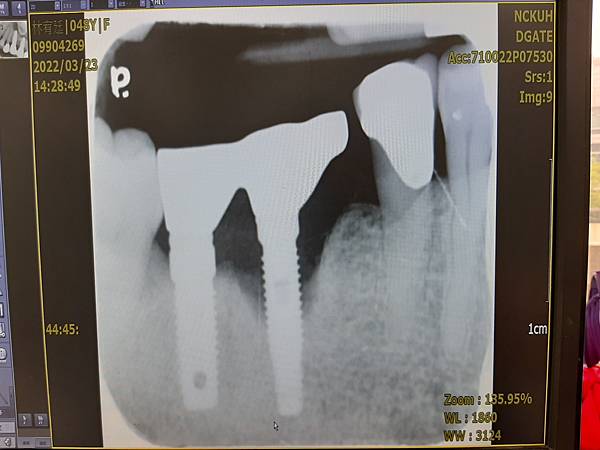

老天爺呀! 我為什麼要承受這麼多的苦難呀! 我第四次因為車禍 門牙兩顆植牙 還未完工

竟然被宣判 要植牙第五次(不同牙齒啦!) ~我人生的第五次植牙又要走一遭!

啊~我竟然又來了我人生的第四次植牙~天呀! WHY~?

~車禍了!